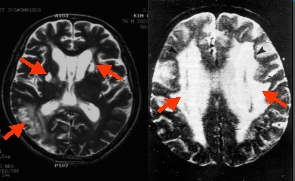

뇌혈관 손상, 알코올 과다 섭취, 흡연, 과도한 스트레스는

심각한 뇌손상을 가져올 수 있습니다.

한번 파괴된 뇌 세포는 복구가 불가능한데요.